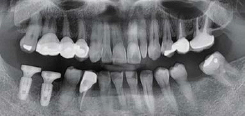

Multiple implants & bridge

술 전 파노라마

술 후 파노라마